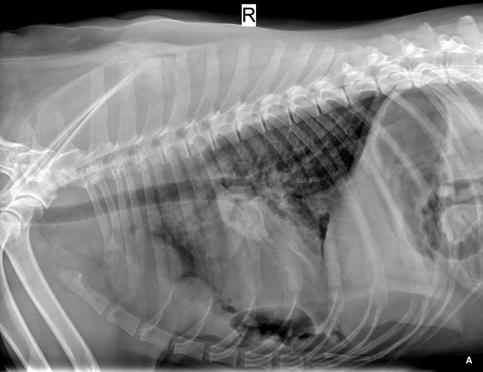

Se realiza radiografía de tórax (Fig. 1) que revela car-

diomegalia generalizada severa, índice de Buchanan de 15 cuerpos vertebrales, que puede corresponder a un severo aumento de las cámaras cardiacas, o a la presencia de líquido pericárdico. Se observa, además, un patrón pulmonar intersticial perihiliar, compatible con edema pulmonar, foco de neumonía o hemorragia pulmonar.

M. López,1 V. Fernández,2 J. Engel3 1Servicio de cardiología y diagnóstico por imagen. 2Servicio de cirugía. Laclinicaveterinaria. c/Marroquina 26. 28030 Madrid. 3Servicio de cardiología. ANICURA-Benipeixcar Hospital Veterinario. Avinguda de la Constitució 68, bajo izq. 46009 Valencia. ANICURA-San Francisco Hospital Veterinario. c/ Sant Francesc 65. 12500 Vinaròs (Castelló). ANICURA-San Vicente Hospital Veterinario. c/ Veterinario Manuel Isidro Rodríguez García 17. 03690 San Vicente del Raspeig (Alicante). Figura 1. Radiografía lateral de tórax en la que se observa cardiomegalia generalizada, VHS 15. Patrón alveolar intersticial compatible con edema pulmonar. Patrón vascular mixto y patrón bronquial en lóbulos caudales, compatible con bronquitis crónica, mineralización por degeneración senil.

En el caso que presentamos podemos confirmar cardiomegalia severa y edema pulmonar dado que el estudio radiológico del tórax permite establecer el tamaño cardiaco y valorar el patrón pulmonar. La insuficiencia cardíaca congestiva izquierda se caracteriza por un patrón intersticial, que puede evolucionar a patrón alveolar en la región perihiliar que tiende a distribuirse hacia caudodorsal, característico del edema pulmonar cardiogénico, patrón vascular venoso.